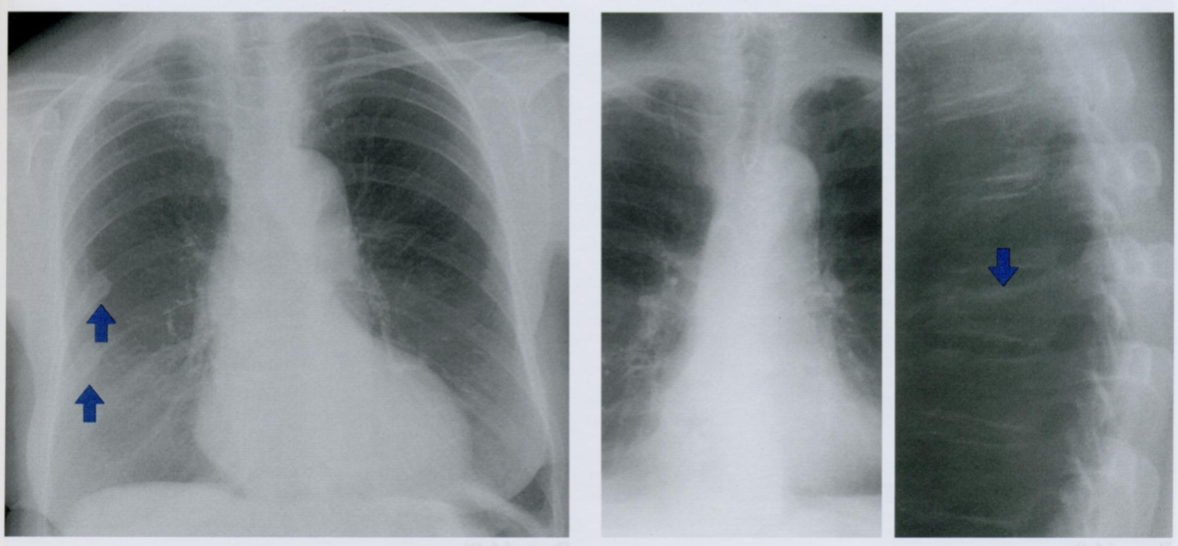

Оцените ассиметричность мягких тканей на снимке.

Обратите внимание на тень молочной железы (стрелочки), оцените симметричность теней слева и справа.

Ассиметрия прозрачности может наблюдаться после мастэктомий, радикального иссечения шейных лимфатических узлов, посттравматической гематомы грудной стенки, гепертрофии/атрофии мышц.

Пациентка после левосторонней мастэктомии с просветлением в нижних отделах с соотвествующей стороны (звездочка) в связи с отсутствием молочной железы (стрелочки).

Если есть сомнения, можно внимательнее рассмотреть подмышечную область на предмет возможного наличия металических клипс после иссечения ЛУ подмышечной впадины (фото ниже).

Ключевой момент - не ошибиться, принимая уменьшение прозрачности с одной стороны за выпот или внутрилегочное образование.